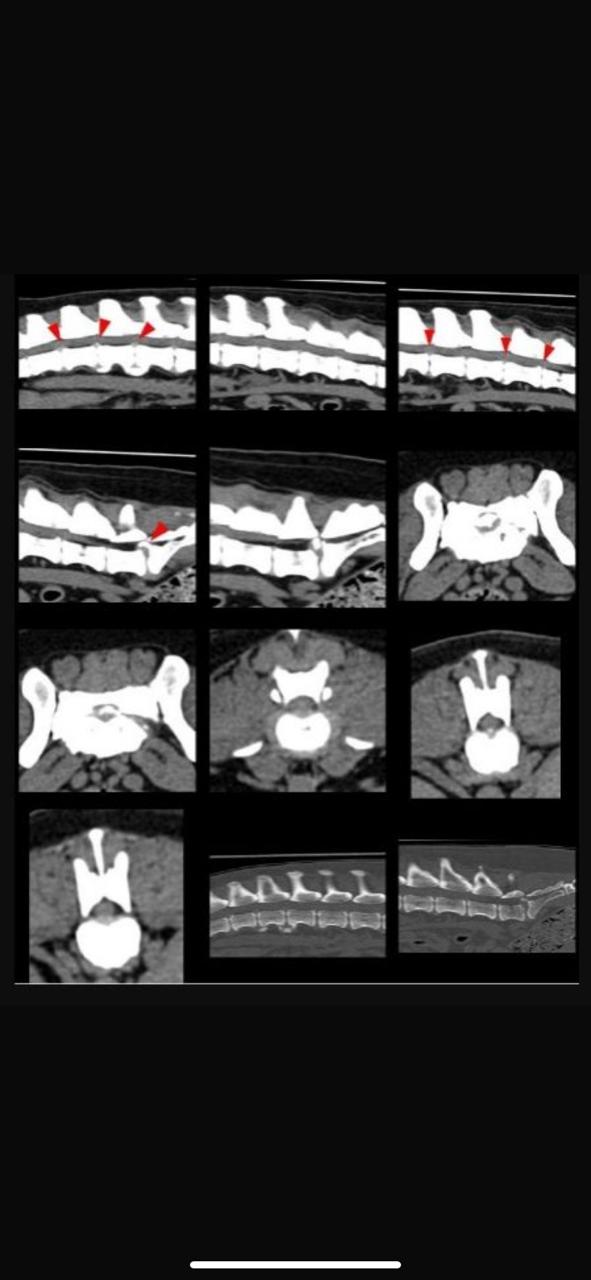

Protrusões nos discos da coluna vertebral, o que está causando MUITA dor a ele 😕